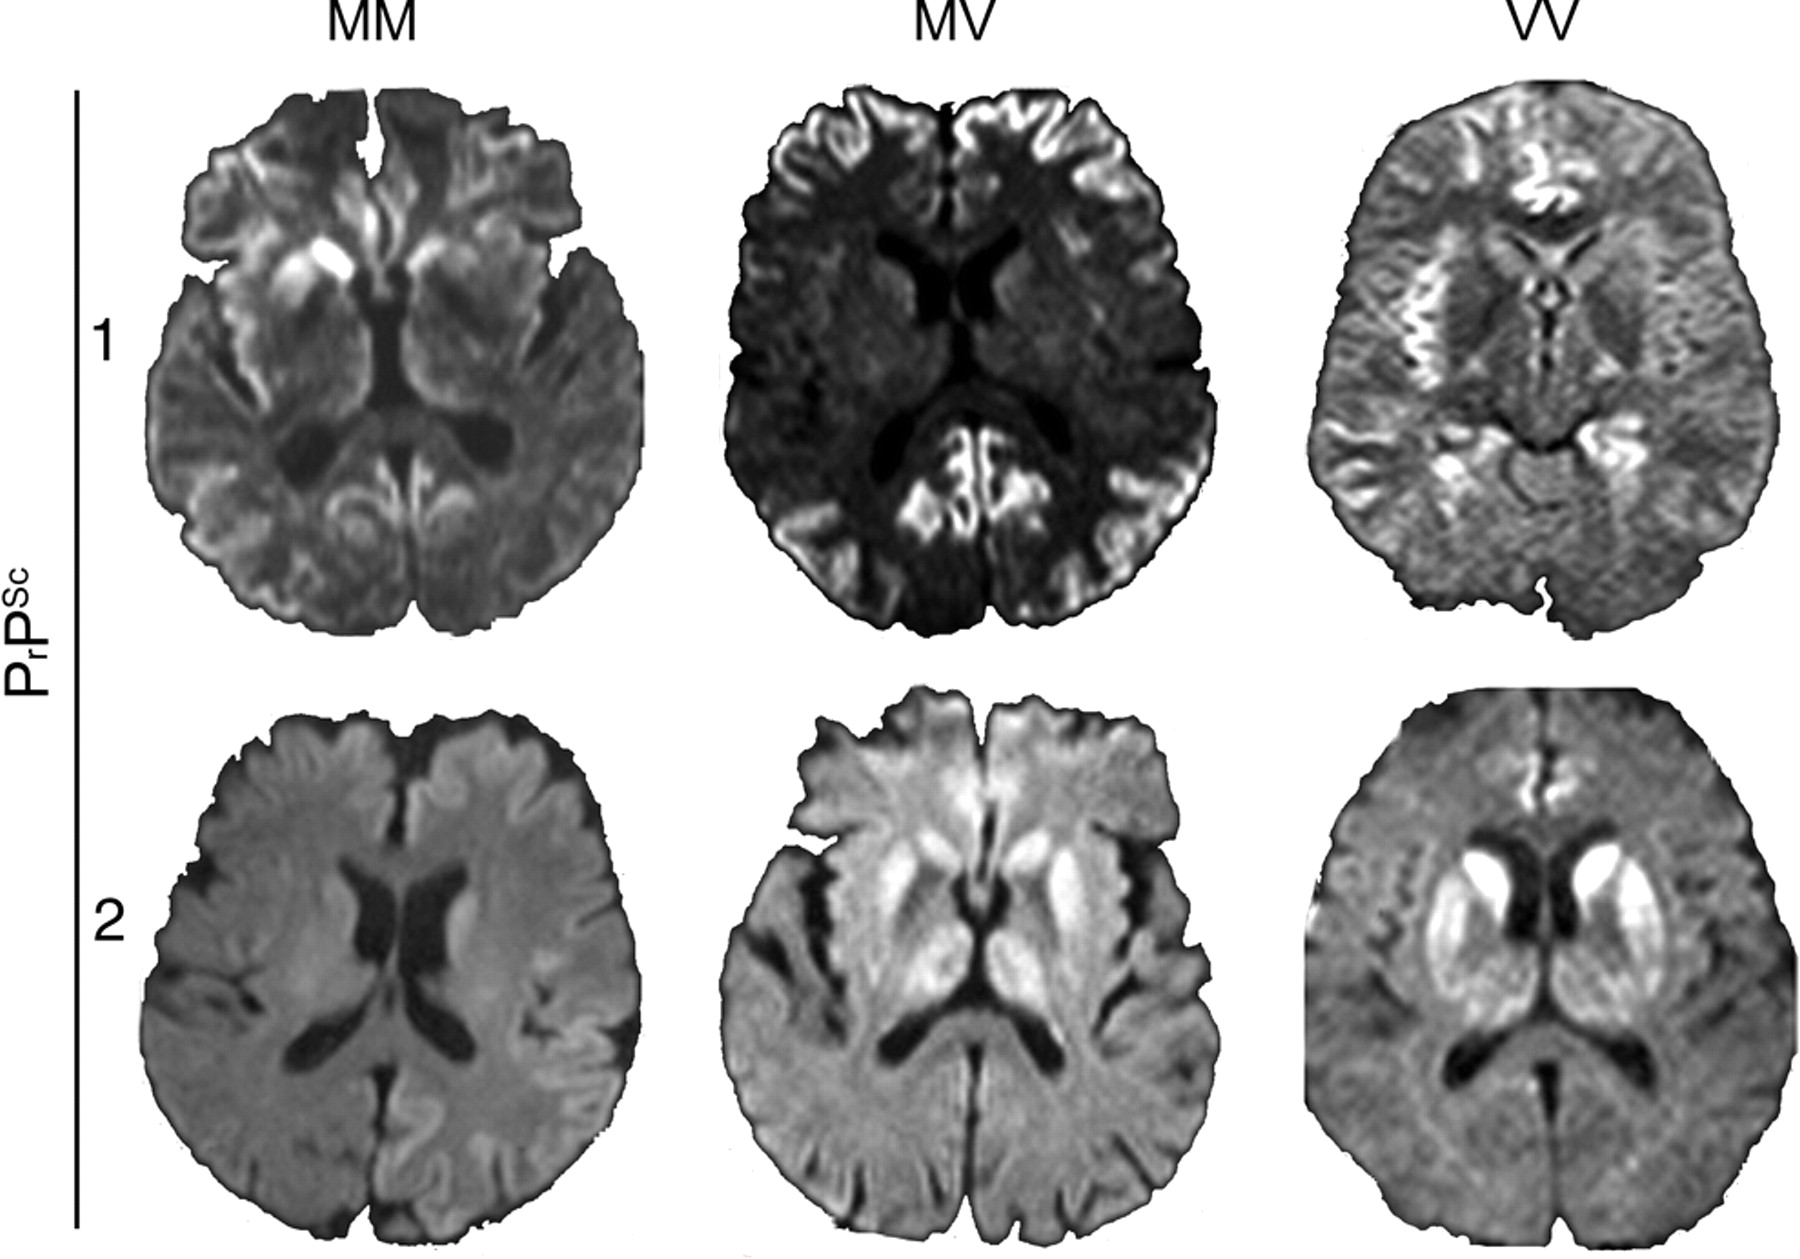

MRI显示例子特点给出亚型的发现图1。的百分比和p显示值用于描述的亚型表1和2和图2。

图1特征核磁共振发现零星克雅二氏症(sCJD)亚型

Diffusion-weighted六sCJD各种分子亚型患者的图像显示基底神经节信号增加和信号额增加,时间,和岛叶皮质(MM1);主要的额叶和顶叶皮层信号增加(1/2 MV1);的扣带回皮质hyperintensities、岛叶皮质和海马体(VV1);基底神经节和广泛的皮质hyperintensities(平方毫米);主要的信号增加基底节和丘脑(MV2);和主要基底神经节信号增加,信号增加扣带回(VV2)。发表在的1/2 MV1映像是J Neuroradiol2008;29:1519 - 1524(©2008美国社会的神经放射学;允许转载)。22VV1图像发表在首页河畔65:1544 2005;1550(©2005企业有限公司;允许转载)。15MV2图像发表在是J Neuroradiol2006;27:1459 - 1462(©2006美国社会的神经放射学;允许转载)。23

图2 MRI病灶模式MM1,平方毫米,1/2 MV1 MV2, VV1 VV2

*见fluid-attenuated反转恢复或diffusion-weighted成像。